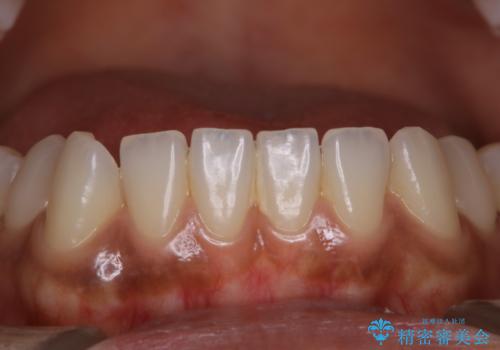

全体的な治療の開始前に着色取り